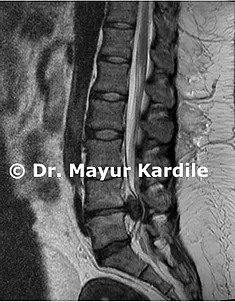

Microdiscectomy is a minimally invasive surgical procedure where the herniated portion of an intervertebral disc is removed using a surgical microscope through a very small incision. This relieves pressure on the compressed spinal nerve and resolves sciatica or arm pain.

- Leg pain or arm pain (sciatica) due to herniated disc persisting for 6+ weeks despite non-surgical treatment

- MRI showing herniated disc at the level causing symptoms